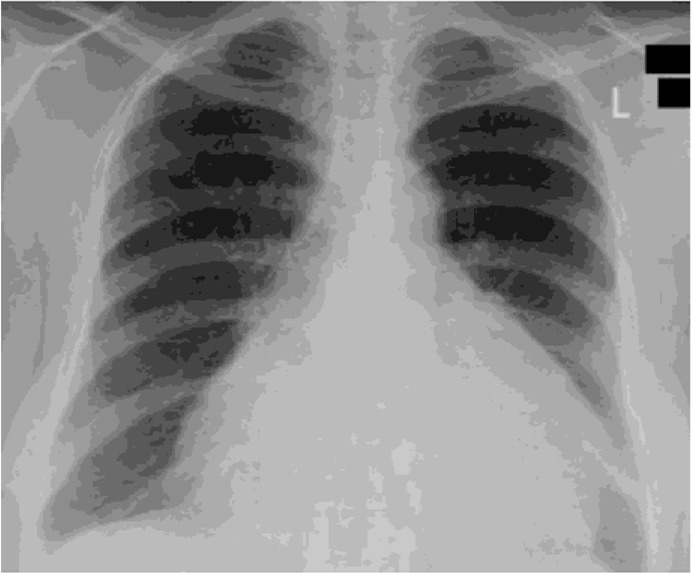

Considerable information is available about the acute respiratory symptoms of influenza A and B. However, rarely, these viruses can adversely affect the cardiovascular system. Few cases of pericardial effusion and cardiac tamponade due to the Influenza virus have been reported. To the best of our knowledge, we present the first case of a 23-year-old unvaccinated woman having concurrent influenza A and B infection manifesting as pericardial effusion and cardiac tamponade. The patient was treated with oseltamivir 75 mg, resulting in significant clinical improvement. This case emphasizes the importance of considering influenza as a possible cause of cardiac tamponade.